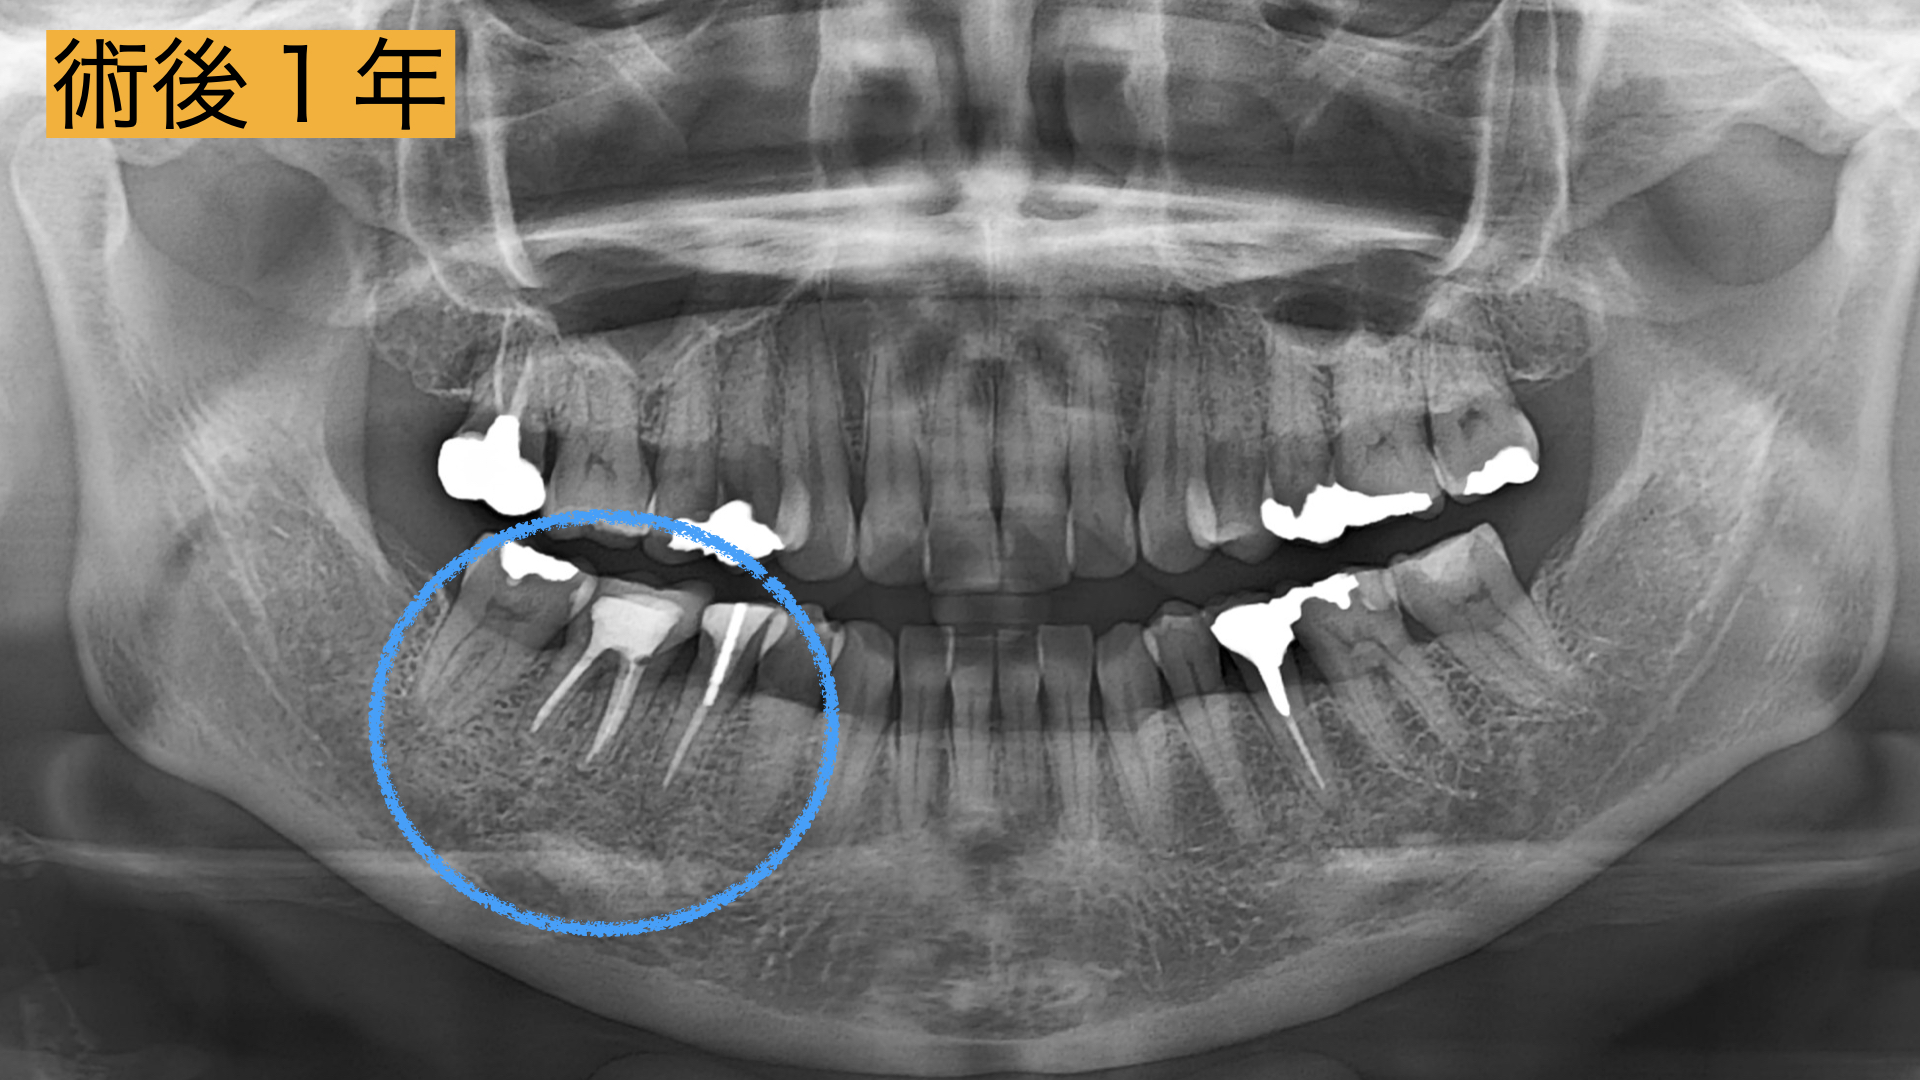

今回、根の治療が3回目とのこともあったため被せ物・土台を外して長期的予後が見込める場合は精密根管治療、見込めない場合は抜歯してブリッジ治療。と決定いたしました。

術後

術直後から痛み、腫れは、解消し2年間の経過観察も問題なく過ごせましたとのことでした。 レントゲンで骨の回復が確認とれ、非常に驚かれておりました。